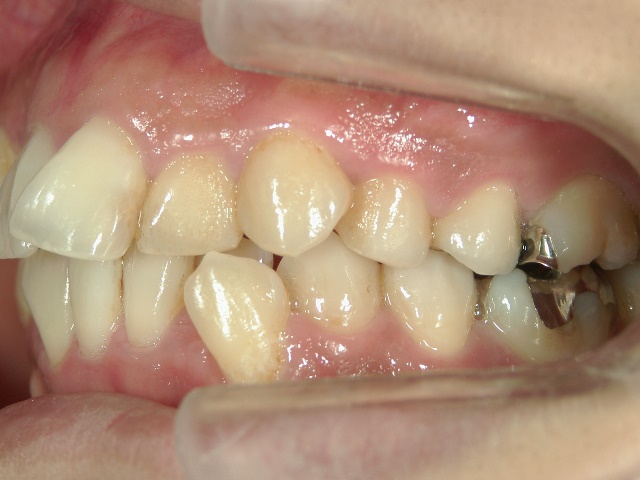

矯正歯科 治療後矯正歯科 全顎ワイヤー矯正 治療後矯正歯科(全顎ワイヤー矯正)治療後

矯正歯科 治療後

no.31_1962_治療後_右.JPGno.31_1962_治療後_正面.JPGno.31_1962_治療後_左.JPG